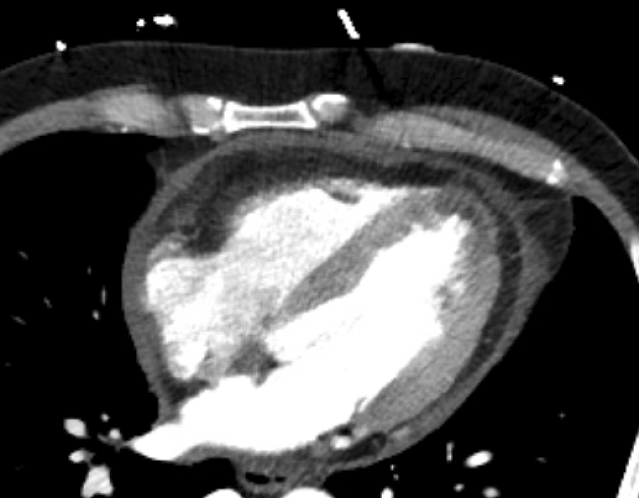

Middle-aged male presents with chest pain. Pt reports waking up at 3 am with non-radiating pleuritic and constant pressure-like epigastric pain, which he has never had before. Pain is better with lying flat, worse with sitting up and leaning forward. Feels some SOB, but no CP. No recent travel, but possibly has had recent viral cold symptoms in the past 24 hours. Denies cardiac hx. Denies recent travel or hospitalizations.

Impression:

1. No aortic aneurysm or acute aortic pathology.

2. Pericardial effusion, with pericardial thickening and enhancement and

adjacent fat stranding highly suspicious for acute pericarditis. Recommend

follow-up echocardiogram for further characterization.

3. Small subendocardial fat in the distal left ventricular anterior wall,

may represent normal variant versus sequelae of previous myocardial

infarct.